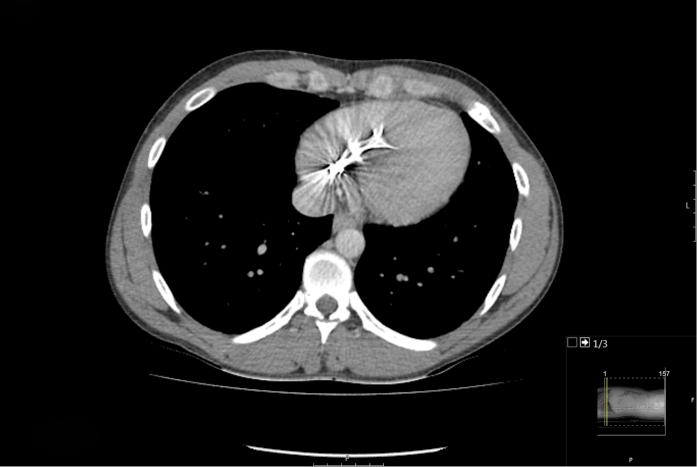

We describe a case of an adult patient with embolization of a varicocele coil (7 × 70 mm) to the right ventricle. We review the multimodality imaging techniques used to identify location and the importance of a multidisciplinary approach in determining management. ().

我们描述了一例成年患者,其精索静脉曲张线圈(7×70毫米)栓塞至右心室。我们回顾了用于确定位置的多模态成像技术以及多学科方法在确定治疗方案中的重要性。()